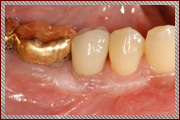

症例1

右下の奥歯の失った部位に対して、痩せた歯茎の再生治療とインプラント治療を行いました。